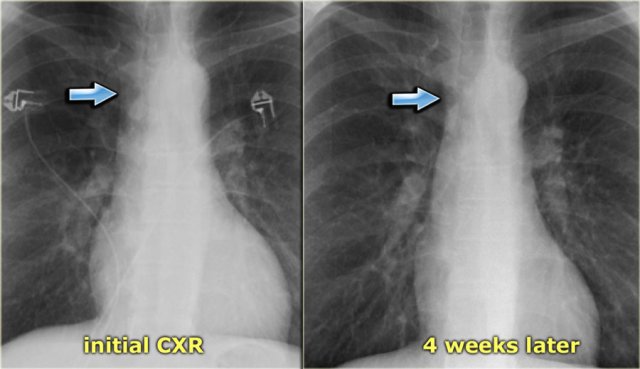

On the left a patient with subtle signs of congestive heart failure on the initial chest x-ray (image 1/2).

There is a slightly enlarged vascular pedicle, which becomes more obvious when you compare to the chest film after diuretic therapy (image 2/2).